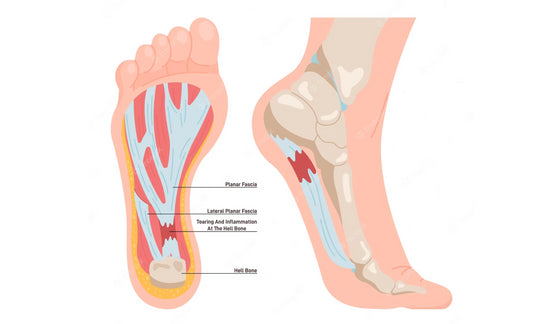

SKU: OmegaFoot